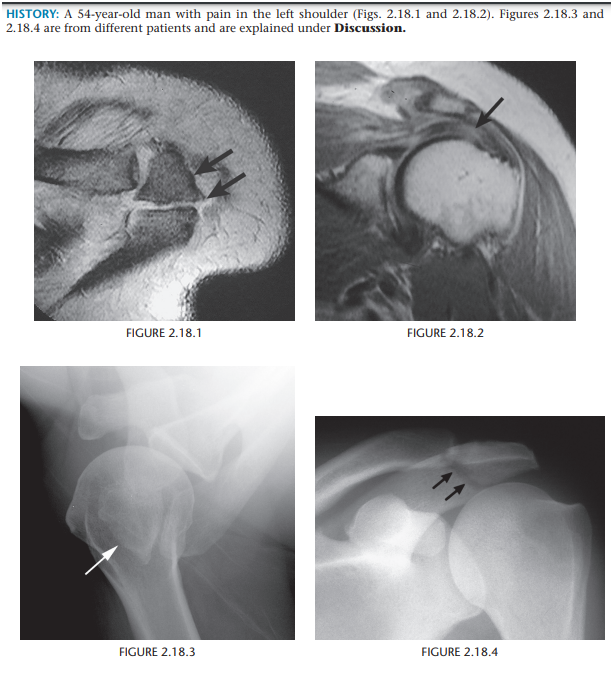

Pigmented Villonodular synovitis

e hemosiderin deposits, generally have low signal intensity on T1- and

T2-weighted MR images - seen also in hemophilia

“chocolate” effusion